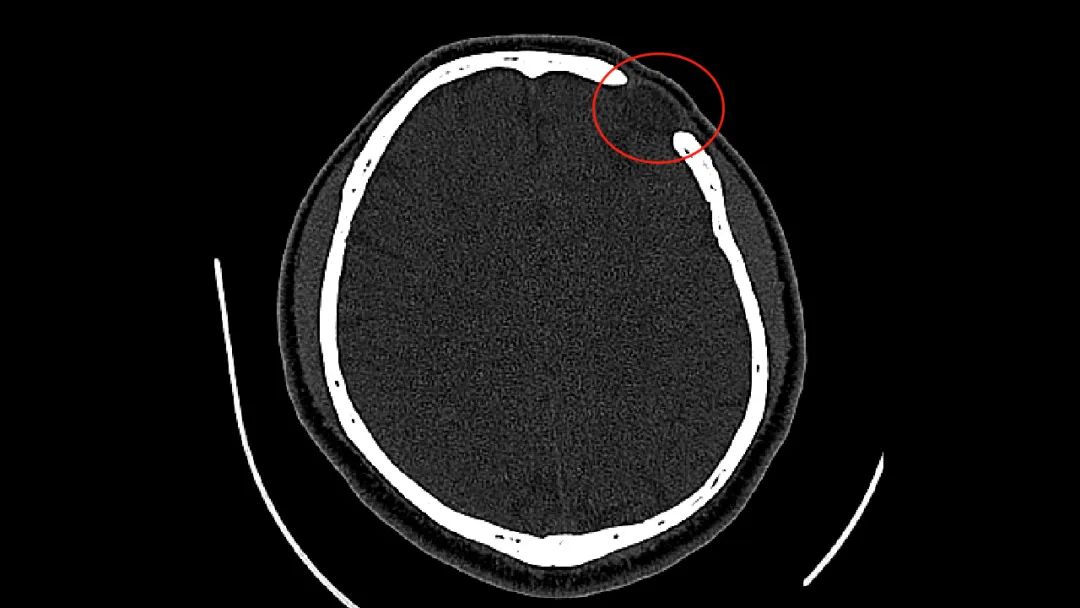

CT显示李先生前额颅骨缺损

李先生颅骨缺损面积不算太大,有20平方cm左右,但缺损位置在前额,并略有塌陷,看起来挺明显。这部分颅骨缺损,对李先生的工作、生活影响很大,导致他心理上很自卑。

穆苍山主任接诊后,对李先生病情进行详细诊断评估,实际测量颅骨缺损面积为5.5cm*4.5cm。穆主任表示,按照神经外科指南要求,颅骨缺损区域直径大于3cm的,一般建议及时进行颅骨修补。穆主任介绍说,“这位患者颅骨缺损面积较大,且位于前额敏感位置,影响外观美容,对患者心理有一定伤害,符合颅骨修补手术指征。”